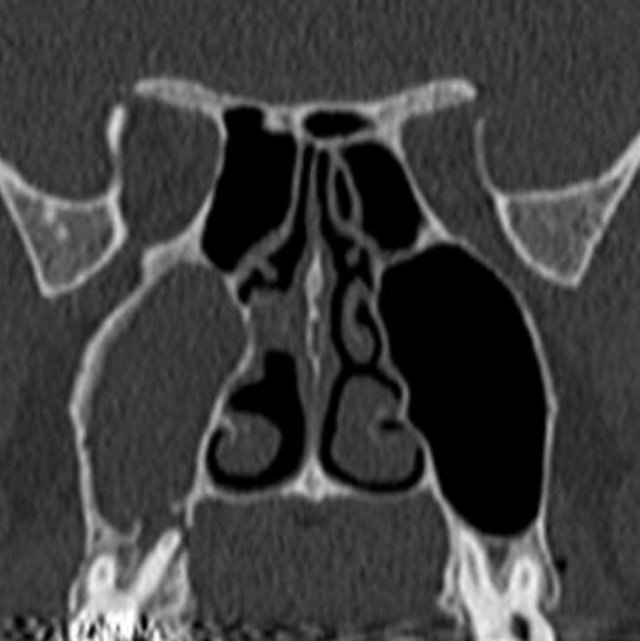

Imagem de tomografia computadorizada em janelamento de ósseo, no plano coronal, demonstando Obliteração total do seio maxilar direito, associado comunicação oroantral, caracterizada por descontinuidade da da membrana de Schneiderian, com da perfuração do assoalho do seio.